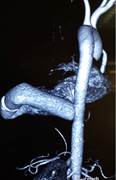

Kết quả siêu âm tim qua thành ngực cho thấy hình ảnh sùi van động mạch chủ, áp xe thành trước động mạch chủ lan tới 1/3 trên vách liên thất gây hở chủ nhiều. Sùi van hai lá gây hở hai lá nhiều và giãn các buồng tim (Hình 1,2). Điện tim đồ cho thấy block nhĩ thất cấp 3 (Hình 3). Cấy máu cấp ở 3 vị trí khác nhau cho kết quả âm tính. Bệnh nhân được hội chẩn nội – ngoại khoa và được chỉ định phẫu thuật cấp cứu.

| Hình 1,2: Hình ảnh abscess gốc ĐMC và vách liên thất trên siêu âm tim. | |